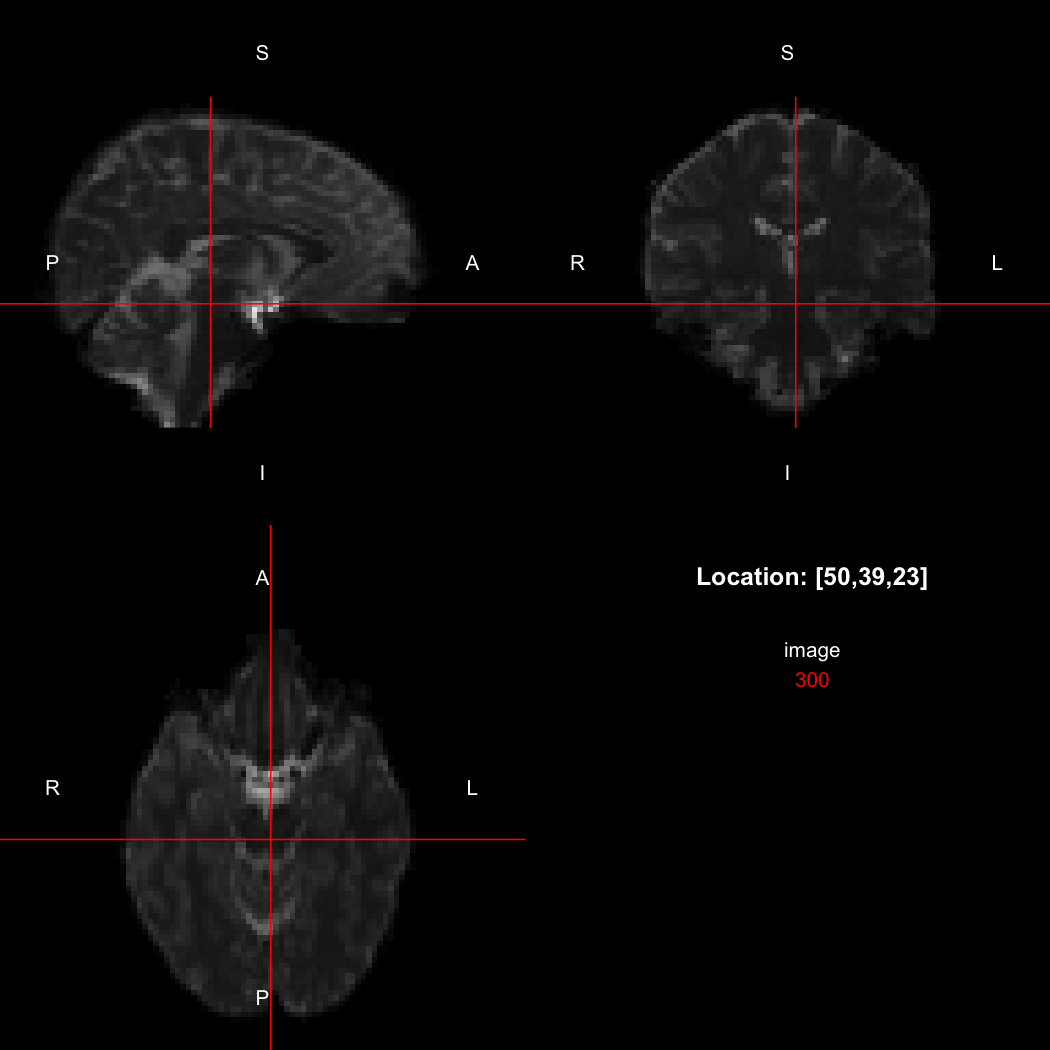

## [1] "LAS"So, here, “LAS” means that the positive x-axis points left, the positive y-axis anterior and the positive z-axis superior. This is the so-called “radiological” orientation convention, and can be requested when viewing images for those who are used to it:

view(image, radiological=TRUE)

Notice the left (L) and right (R) labels, relative to the view shown

above. Setting the radiologicalView option to

TRUE will make this the default for all future views.